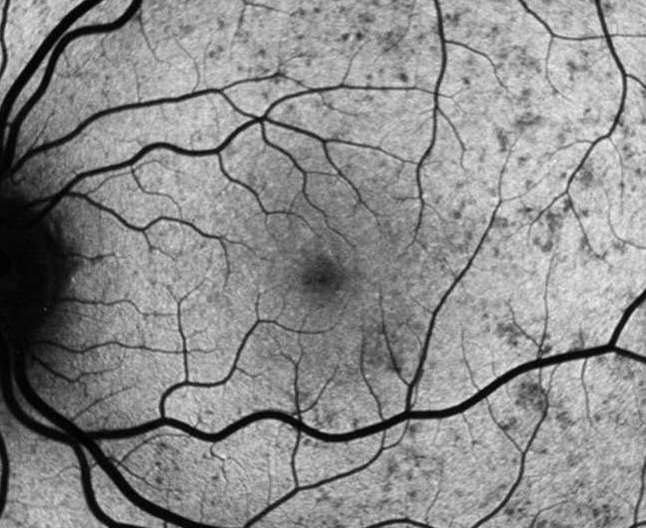

Image Gallery

The AOIP uses a wide range of imaging modalities to study the human visual system.